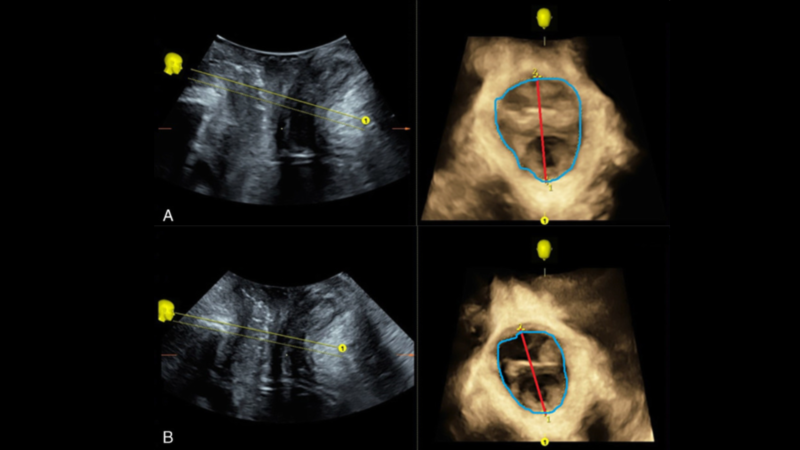

My last 3 sessions were all on protocol 2 which seemed to be working well for me. I did some further research, as I am curious about what these magnetic pulses are doing to my body. I came across this diagram from an independent study in the US showing the narrowing of the pelvic floor cavity and reduction in the thickness of the walls indicating the improved condition of the muscles, seriously impressive!